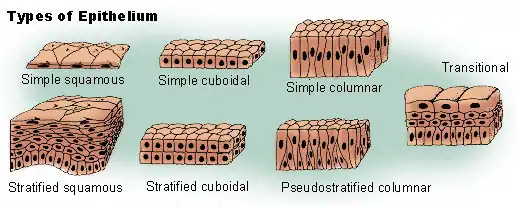

- Nasal lining – At the vestibule, the human nose is lined with a mucous membrane of squamous epithelium, which tissue then transitions to become columnar respiratory epithelium, a pseudo-stratified, ciliated (lash-like) tissue with abundant seromucous glands, which maintains the nasal moisture and protects the respiratory tract from bacteriologic infection and foreign objects.